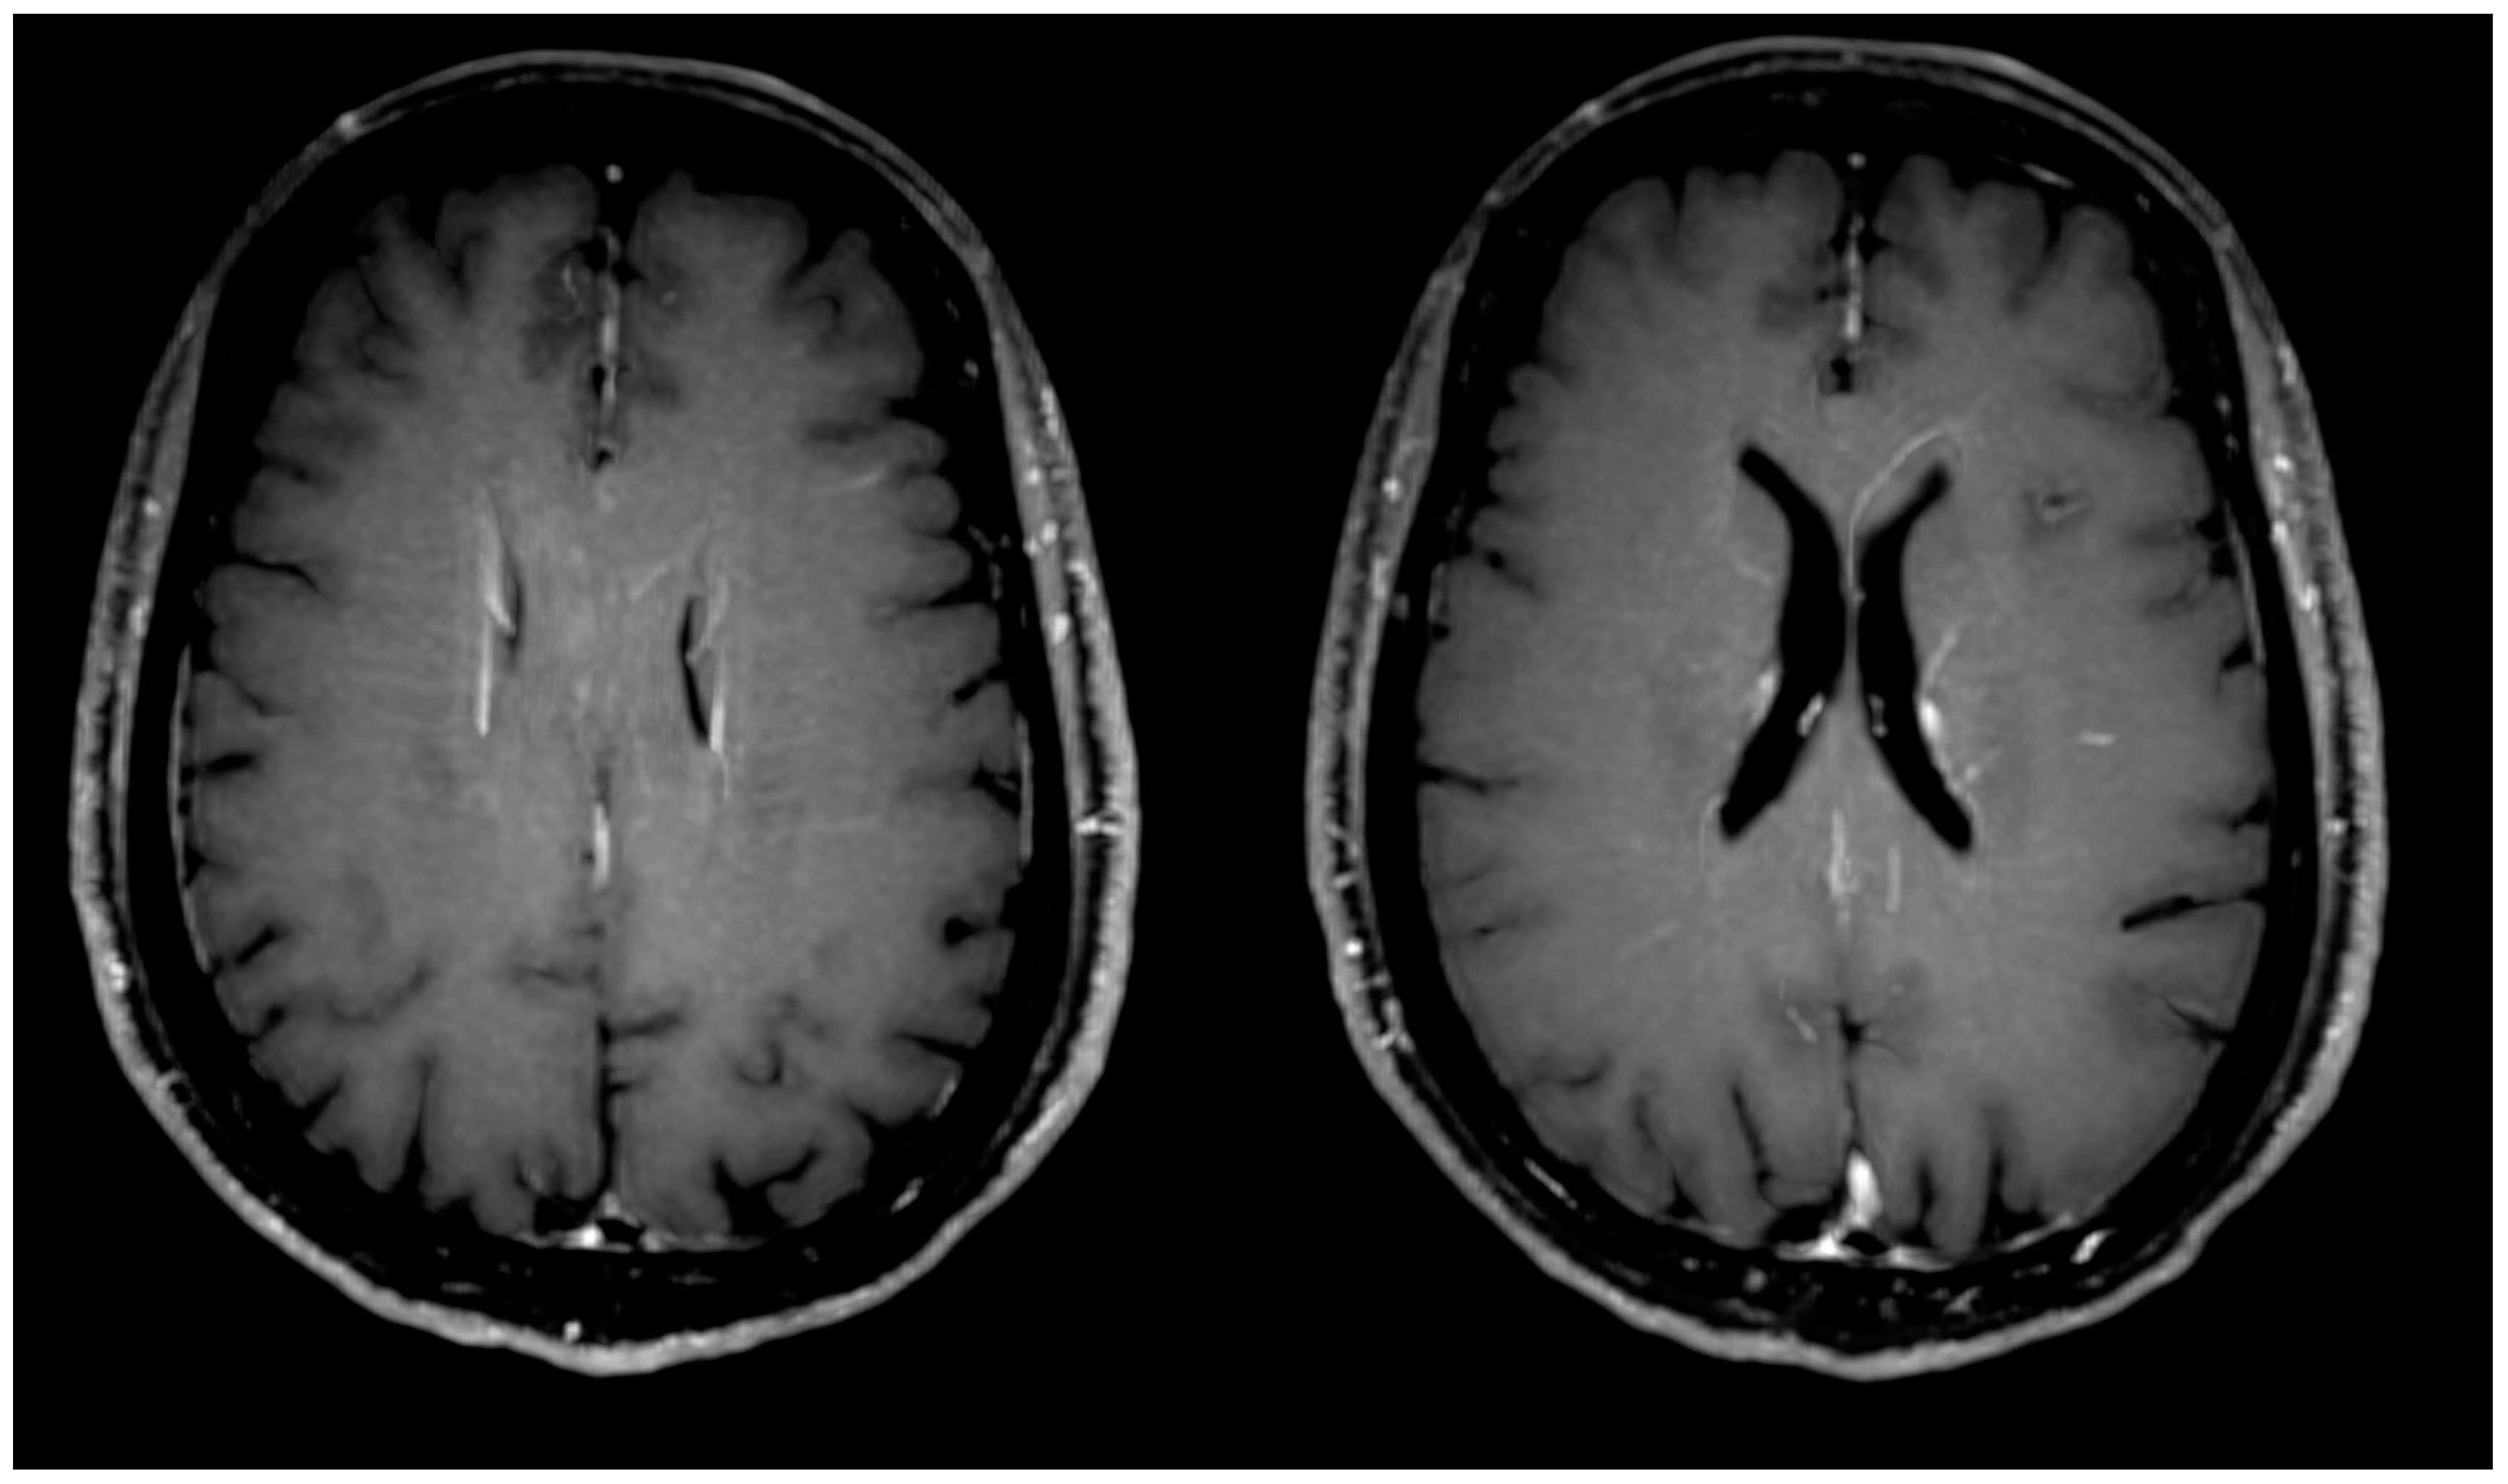

| Presence of inflammatory (concentric) vessel thickening in VWI images | 7 | 30% | ||

| Presence of atherosclerotic (eccentric) vessel thickening in VWI images | 11 | 48% | ||